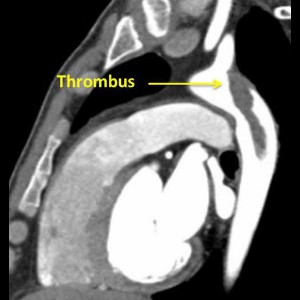

Primary aortic thrombus in young a rare site

Primary aortic thrombus in young: a rare site, a novel treatment

Primary aortic thrombus in young a rare site

Primary aortic thrombus in young: a rare site, a novel treatment